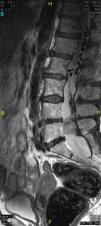

Posteriormente, permaneció asintomática hasta que al cuarto año de seguimiento la paciente recurrió con un dolor lumbociático en la pierna derecha, con una RM lumbosacra que mostró progresión tumoral. Debido al riesgo neurológico de una nueva cirugía, se decidió embolizar la lesión través del pedículo derecho de L4, con lo que se consiguió una gran desvascularización de la lesión. Tras el procedimiento, la paciente permaneció asintomática hasta que al tercer mes reapareció la clínica, momento en que se realizó otra RM que mostró nueva progresión de la lesión, por lo que se decidió una nueva cirugía, en la que se consiguió una resección muy parcial debido a la gran adherencia tumoral y cicatricial a las raíces de L5 y S1, que obligaron a detener la cirugía por riesgo de secuelas neurológicas importantes.

La paciente sigue actualmente con controles clínicos semestrales y radiológicos anuales, encontrándose asintomática y sin crecimiento de la lesión (figs. 4 y 5).